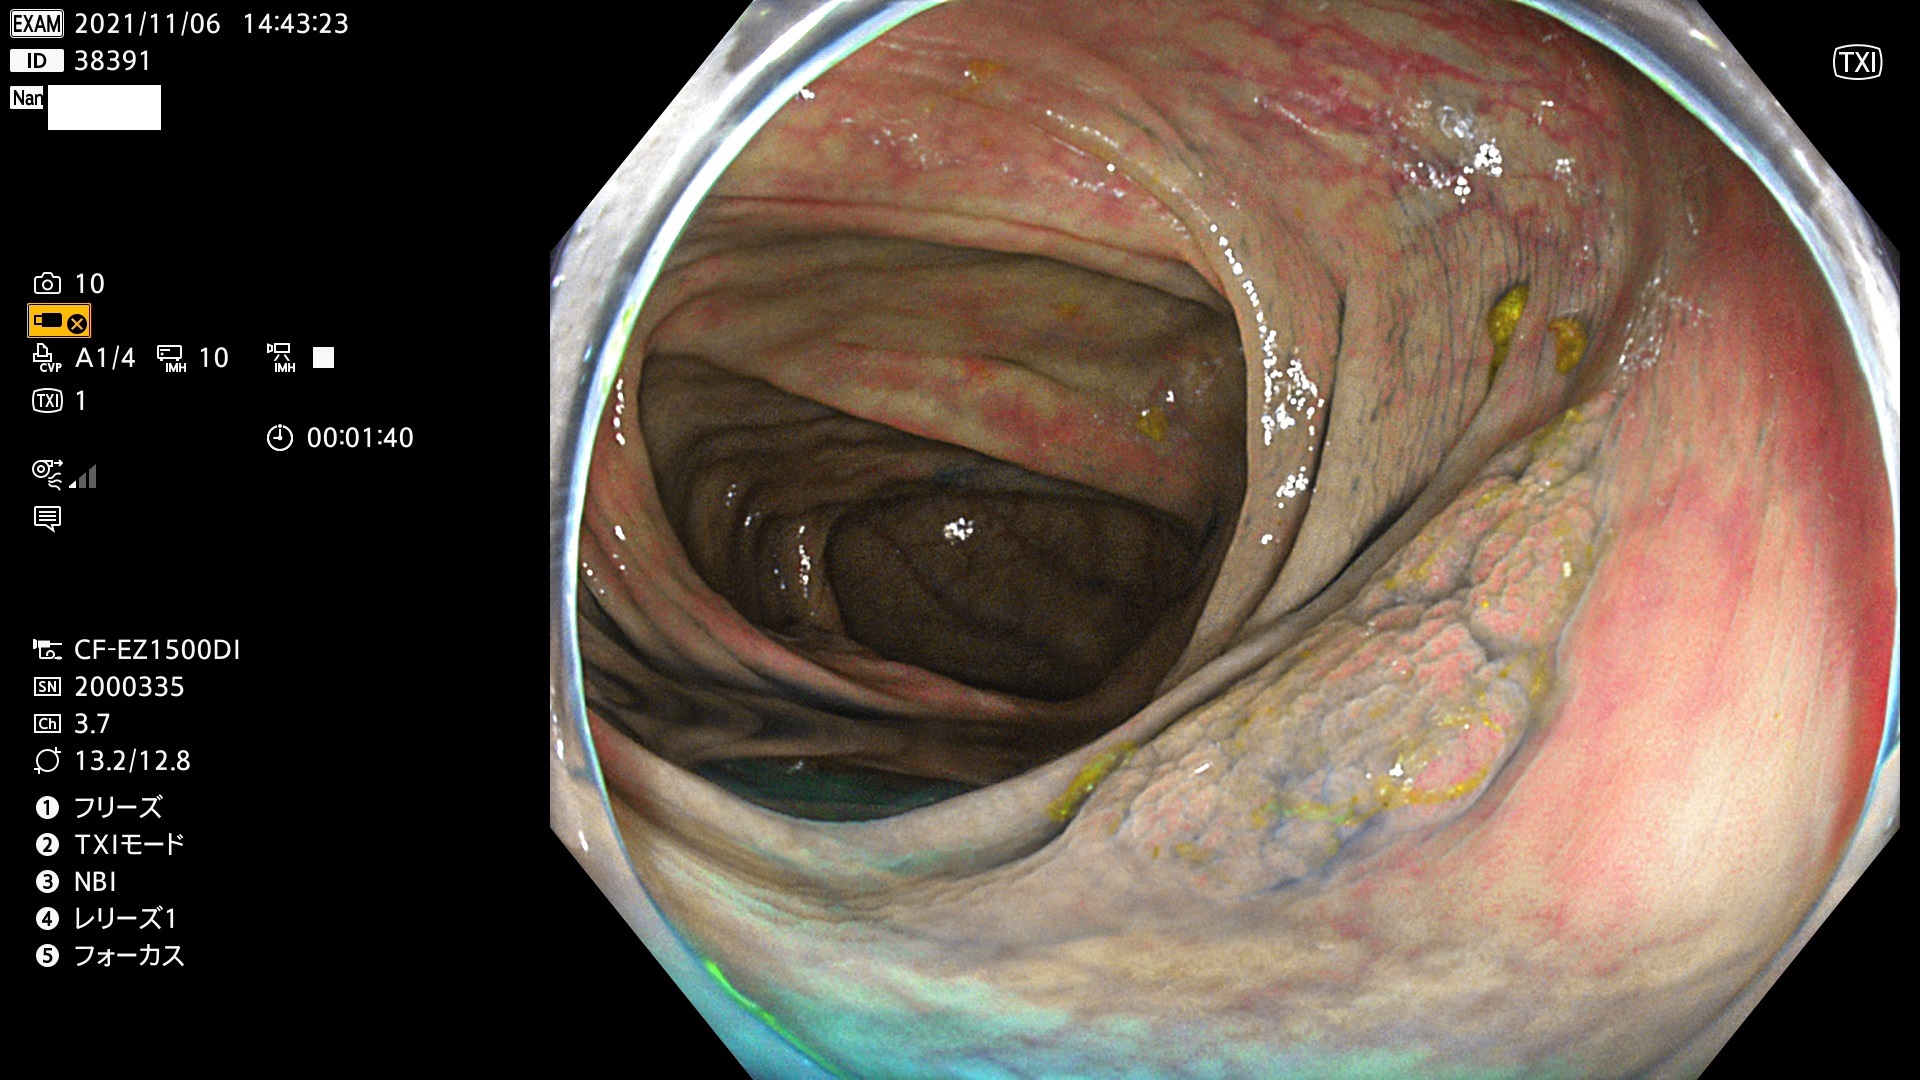

38300 38301 38302 38303 38304 38306 38307 38308 38309 38310 38311 38312 38313 38314 38315 38316 38317 38319 38321 38322 38323 38324 38325 38327 38331 38332 38333 38334 38337 38338 38339 38340 38341 38343 38346 38348 38349 38350 38351 38352 38353 38354 38355 38358 38359 38360 38361 38362 38363 38365 38366(SSAP) 38368 38369 38370 38371(SSAP) 38372 38374 38375 38376 38377 38378 38380 38381 38382 38383 38384 38385 38386 38388 38389 38391(SSAP) 38395 38397 38399

発見困難で危険性の高い平坦型病変(上記100名より抽出)